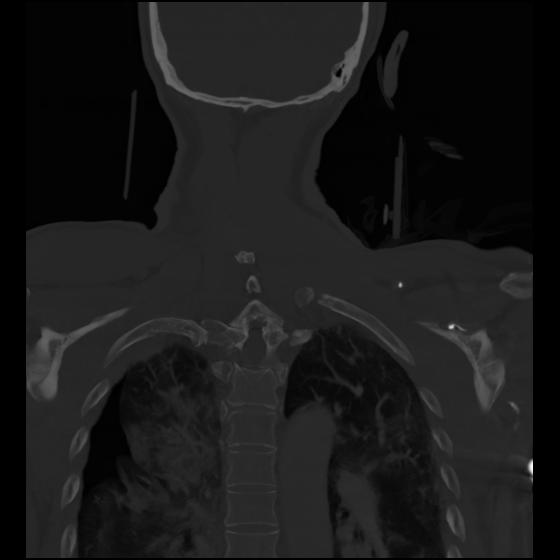

23 ANGIO,CE,Cor-MIP,5.000,ANGIO,Cor-MIP,